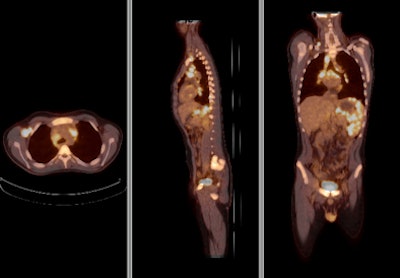

![]() |

| FDG-PET/CT with integrated contrast CT shows a large tumor in the left lung with hilar lymph node metastases. Image courtesy of Siemens Healthcare and the University of Minnesota. |